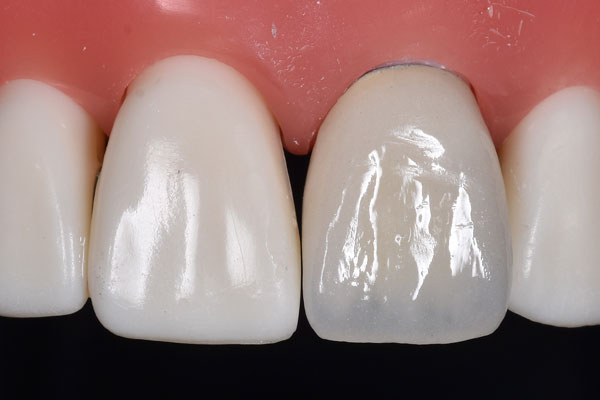

ジルコニアボンド

オールセラミック プレミアム

ジルコニアといわれる硬いフレームの上にセラミックを焼き付けています。

ジルコニアを芯として使っているので強度もあり、周りの歯にあわせてつくるので、とても綺麗で周りの歯になじんだ色味となっています。

ジルコニアボンドの特徴

費用

価格 165,000円/本

保証期間 5年